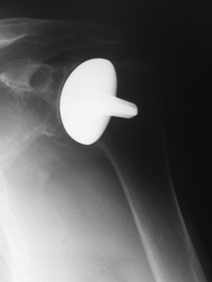

Die Arthrose des Schultergelenkes (Knorpelverschleiß) führt zu Schmerzen und Bewegungseinschränkungen. Während in frühen Stadien manchmal eine arthroskopische Operation Linderung verschaffen kann, ist dies in fortgeschritteneren Fällen nur durch eine Endoprothese möglich. Bei der Schulter haben sich hier der Oberflächenersatz und die Totalendoprothese bewährt. Da bei der Operation ein Muskel (Subscapularis) vorübergehend abgesetzt und am Ende der Operation wieder am Knochen befestigt wird, muss die Schulter für sechs Wochen nach der Operation in einer Schlinge auf einem Kissen teilweise ruhiggestellt werden.